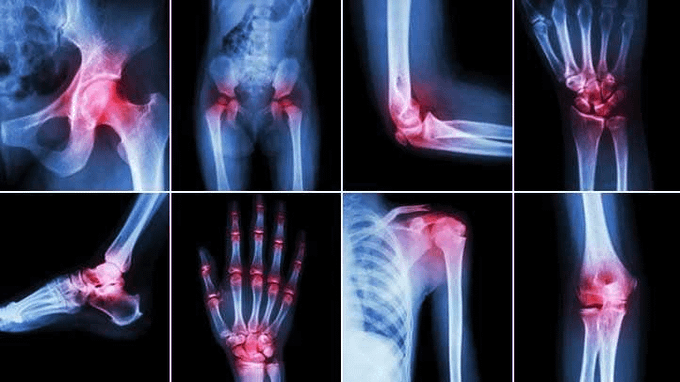

كل واحد عمره فوق الـ 35 يلوم كبر السن على تيبس مفاصله والأوجاع اللي يحس فيها. بس الحقيقة الموضوع مو موضوع عمر.. السالفة وما فيها هي سنين من الإهمال بدت تطلع نتايجها الحين. إليك 8 حلول بسيطة عشان ترمم مفاصلك وترجع تحس إن عمرك 25 من جديد: